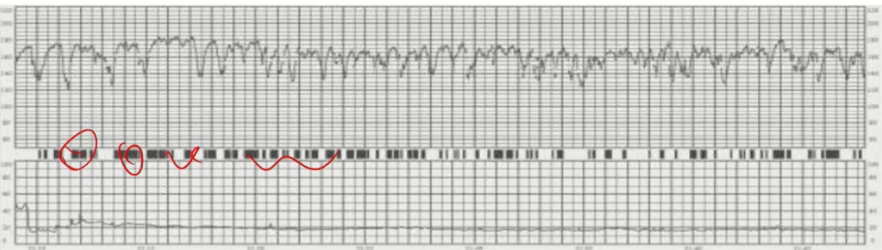

Q

Interpretação dessa variabilidade

A

Acentuada/saltatória

Classificação dessa CTG

Tipo 3